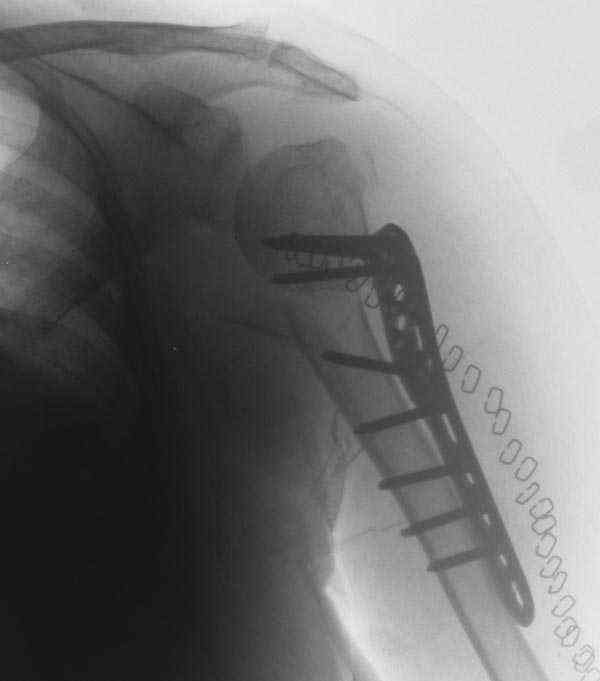

I am attaching the radiographs of the mother of a doctor. She has chronic renal failure for >10 years, diabetes mellitus and coronary artery disease. Age 62. She was offered the options of non-surgical management in a sling and surgery with a locking plate. She was given Tramadol for pain relief. Five days after injury, patient requested surgery, because of pain, inability to move without pain.

The reduction is not perfect. The patient is very small made, and it was difficult to bring the plate proximally without impingement in abduction.

Pain relief after surgery was early and sustained.